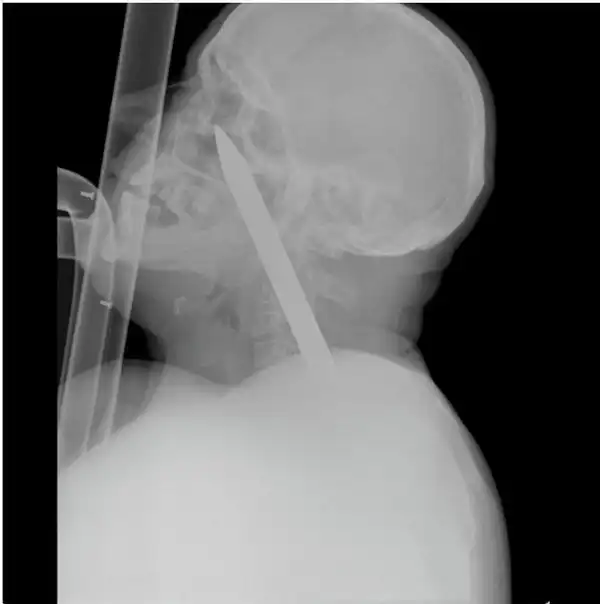

Мужчина упал на лом не повредив жизненно важных органов, говорят после операции выписан в удовлетворительном состоянии домой.